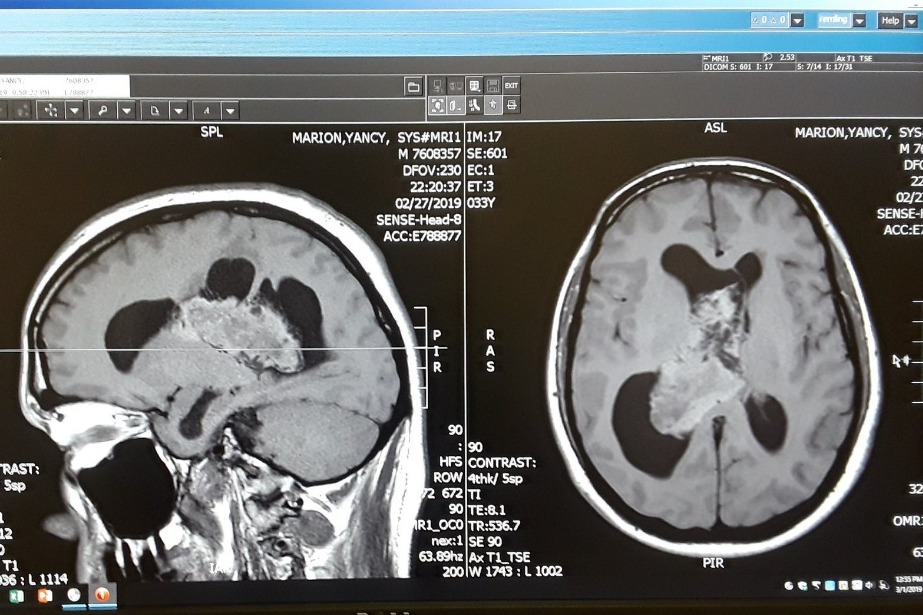

Yancy was diagnosed with a mass in his brain on Feb 28, 2019 after suffering from sever headaches, exhaustion, and double vision . The mass was later confirmed to be a brain tumor.

Despite the terrifying circumstance, Yancy hasn't lost his sense of humor! "Larry", as Yancy calls his brain tumor, is being evicted.

Larry is slated to be kicked out on April 3rd. Apparently Larry has been squatting for several years.

Yancy was diagnosed with a mass in his brain on Feb 28, 2019 after suffering from sever headaches, exhaustion, and double vision . The mass was later confirmed to be a brain tumor.

Despite the terrifying circumstance, Yancy hasn't lost his sense of humor! "Larry", as Yancy calls his brain tumor, is being evicted.

Larry is slated to be kicked out on April 3rd. Apparently Larry has been squatting for several years.